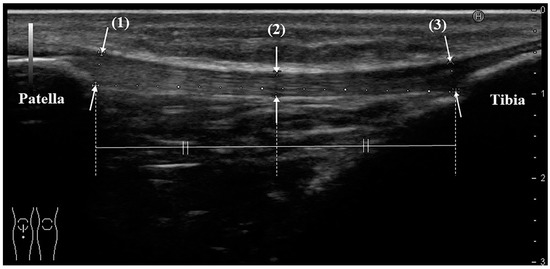

US was performed by the same orthopedic surgeon, who has more than 8 years of clinical experience and who routinely uses ultrasound equipment. The instrument was a HI VISION Preirus (Hitachi Medical Corporation, Kashiwa, Chiba, Japan) and an EUP-L53 linear probe (frequency 7.5 MHz, visual field width 64 mm; the total length of the patellar tendon can be evaluated in 1 slice). The participant was placed in the supine position, and a knee flexion of 30 degrees was achieved by using a knee pillow. Evaluation of the patellar tendon began with the probe being placed at the point where the tendon meets the body surface, and a long-axis image following the entire length of the tendon was drawn. On ultrasound, the tendon should show the typical echogenic, fibrillar pattern and extend from the inferior patella to the tibial tuberosity. The tendon thicknesses at the proximal end, midpoint, and distal end were measured (Figure 1). The measurement was performed 3 times per knee, and the average value was used.

Figure 1. Measurement method of patellar tendon thickness with ultrasonography (long-axis image). Thickness is defined as the distance from the superficial to the deep layers of the tendon, measure at: (1) the proximal part: the point where the deep layer of the tendon is attached to the lower end of the patella; (2) the midpoint between the proximal and distal parts; and (3) the distal part: the point where the deep layer of the tendon is attached to the tibial tubercle. All schemes followed the same formatting.